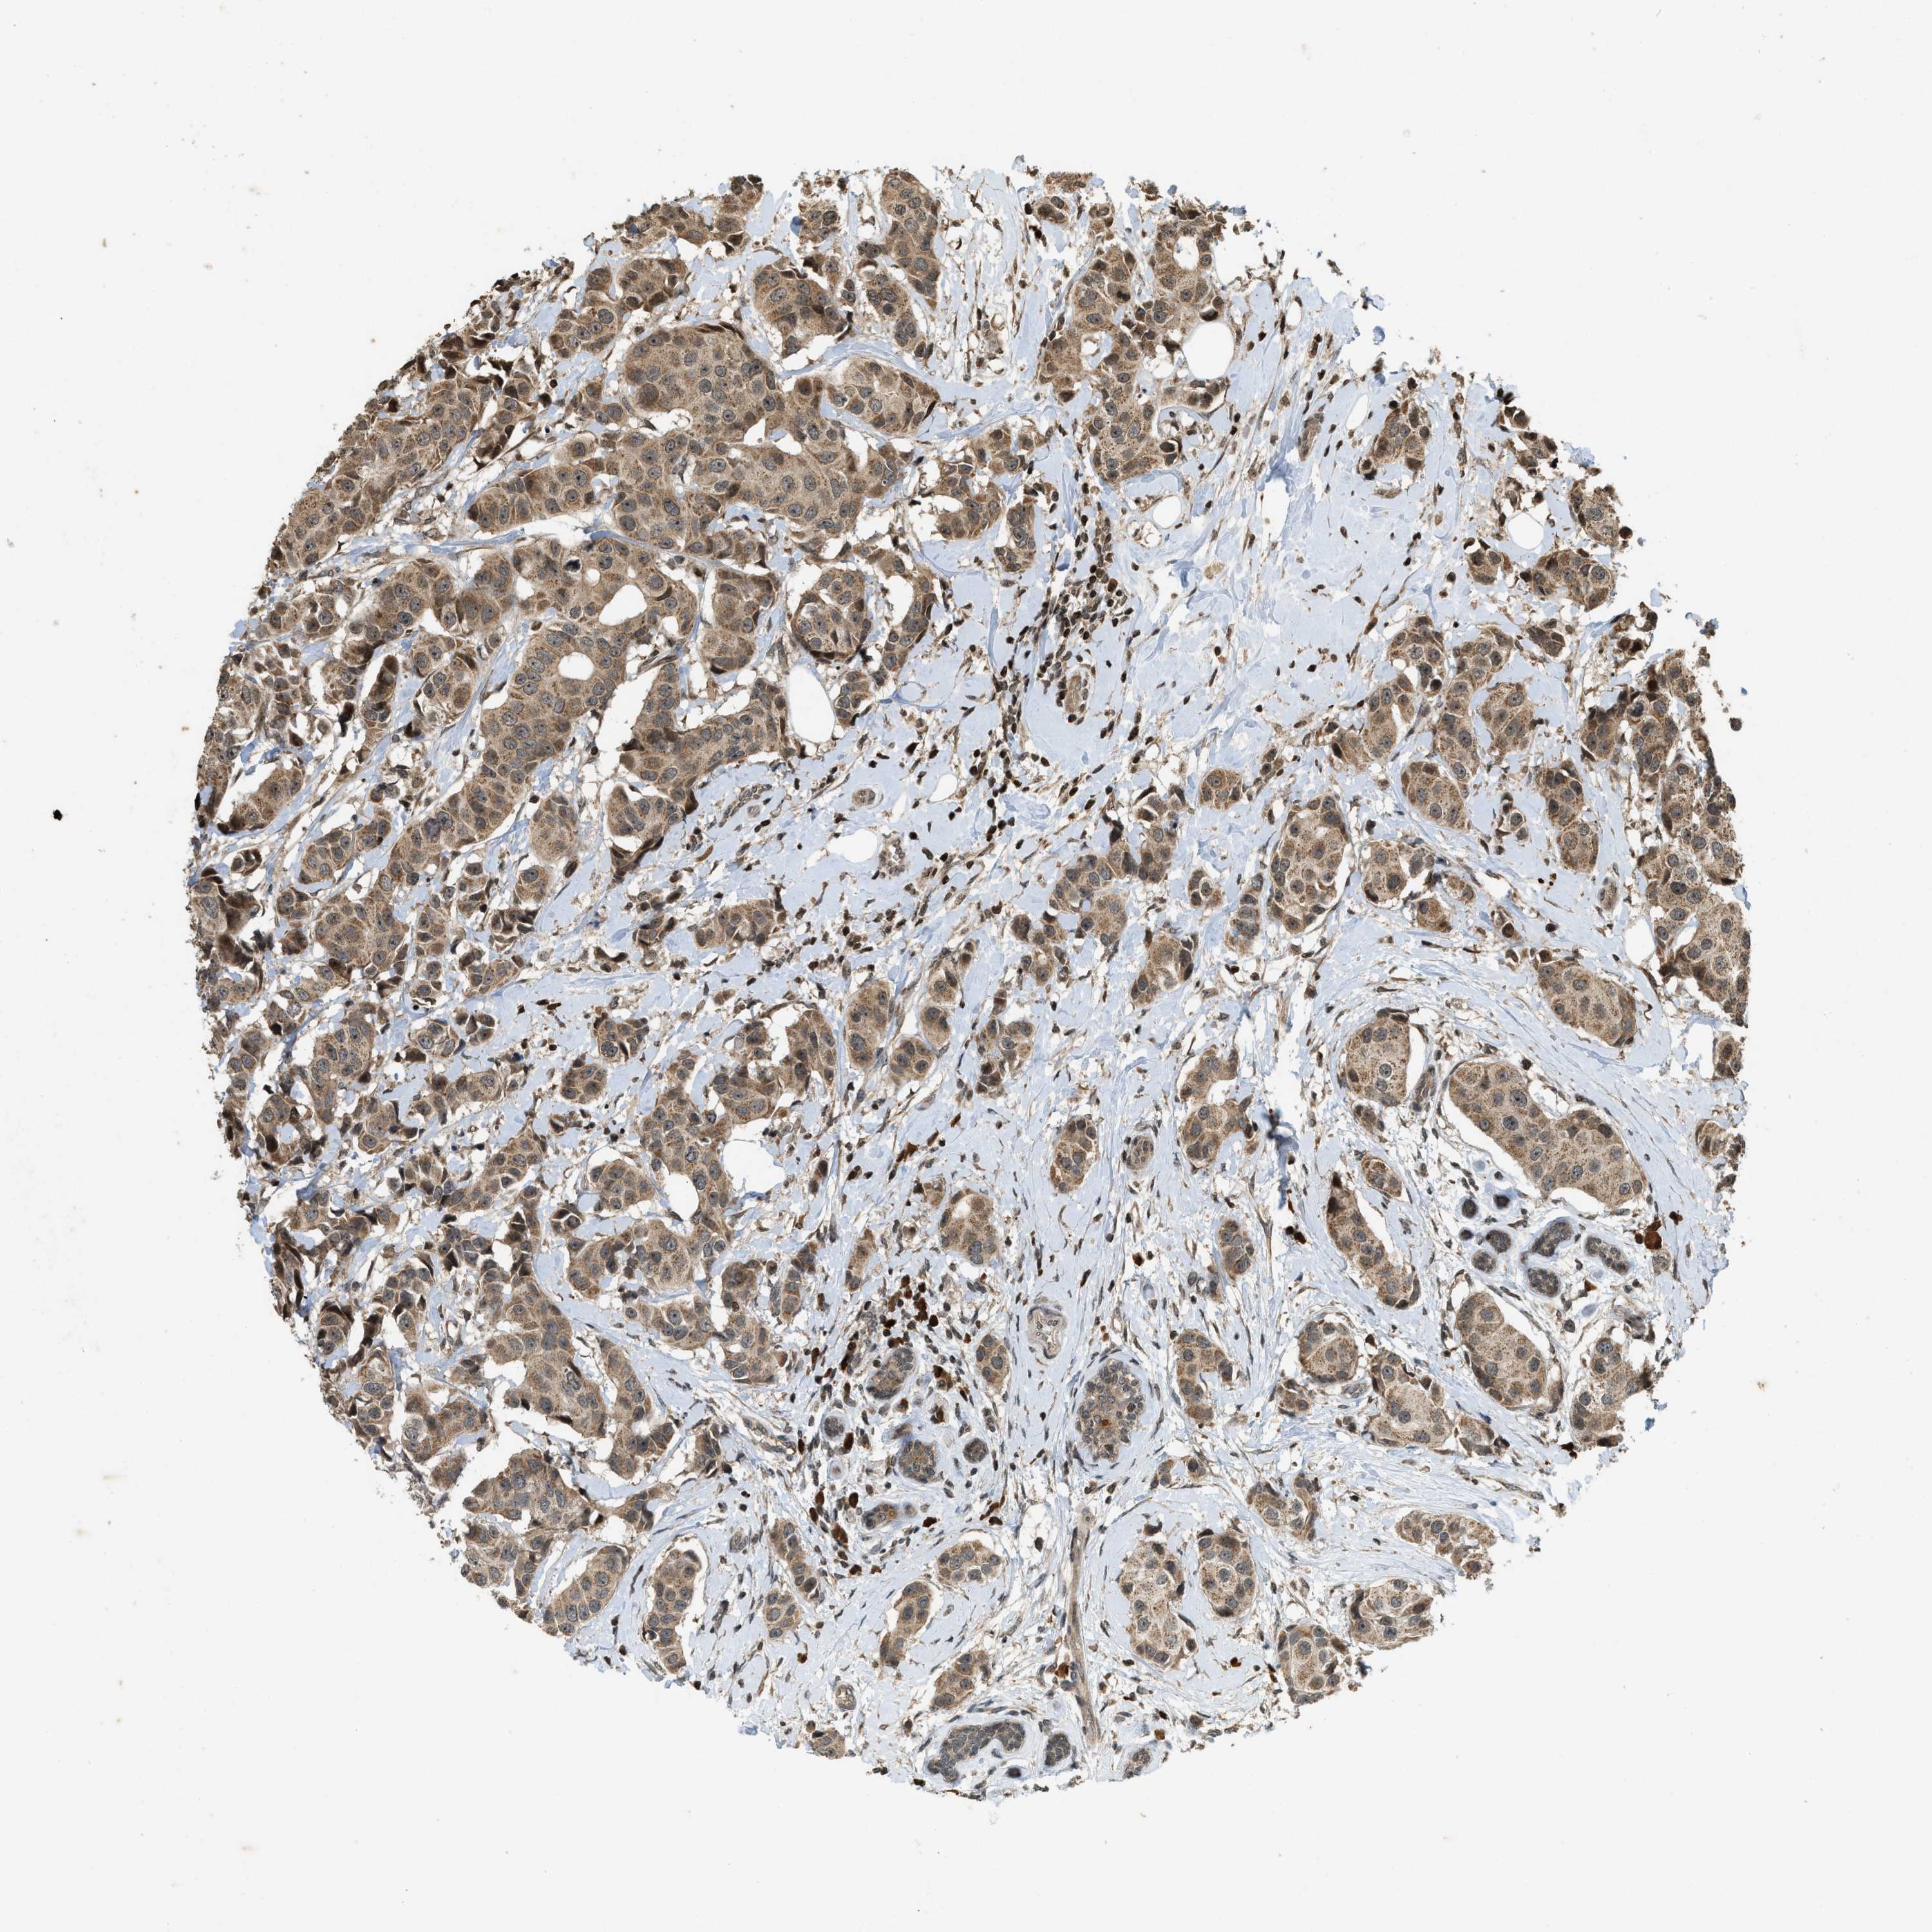

CANCER BREAST CANCER Show tissue menu

BRCA TCGA BRCA VALIDATION PROTEIN EXPRESSION